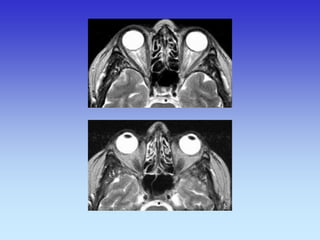

Pituitary Gland

Lens

Cerebral aqueduct

Eye Ball

Optic Nerve

Optic Chiasm

Pons

Cerebellum

Temporal lobe

Lateral Rectus

muscle

Nasal Septum

Cerebral Peduncle

Inferior colliculus

Eye Ball Cerebellum

Eye Ball Third Ventricle Cerebral Peduncle Vermis of Cerebellum Cerebellum